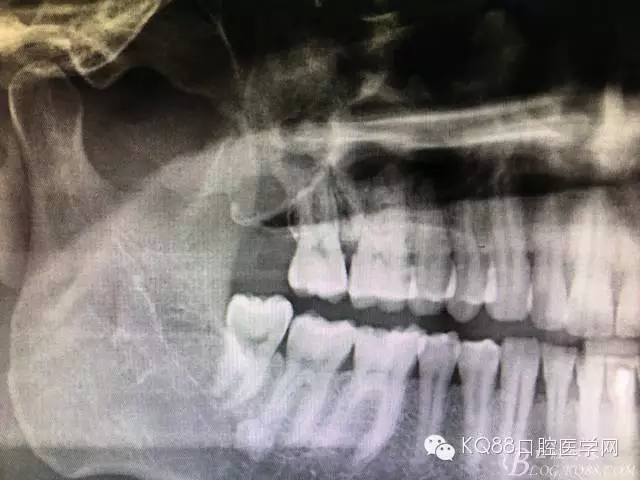

圖18.術(shù)后的全景片影像檢查:

圖19.局部放大影像檢查:17牙根未見損傷